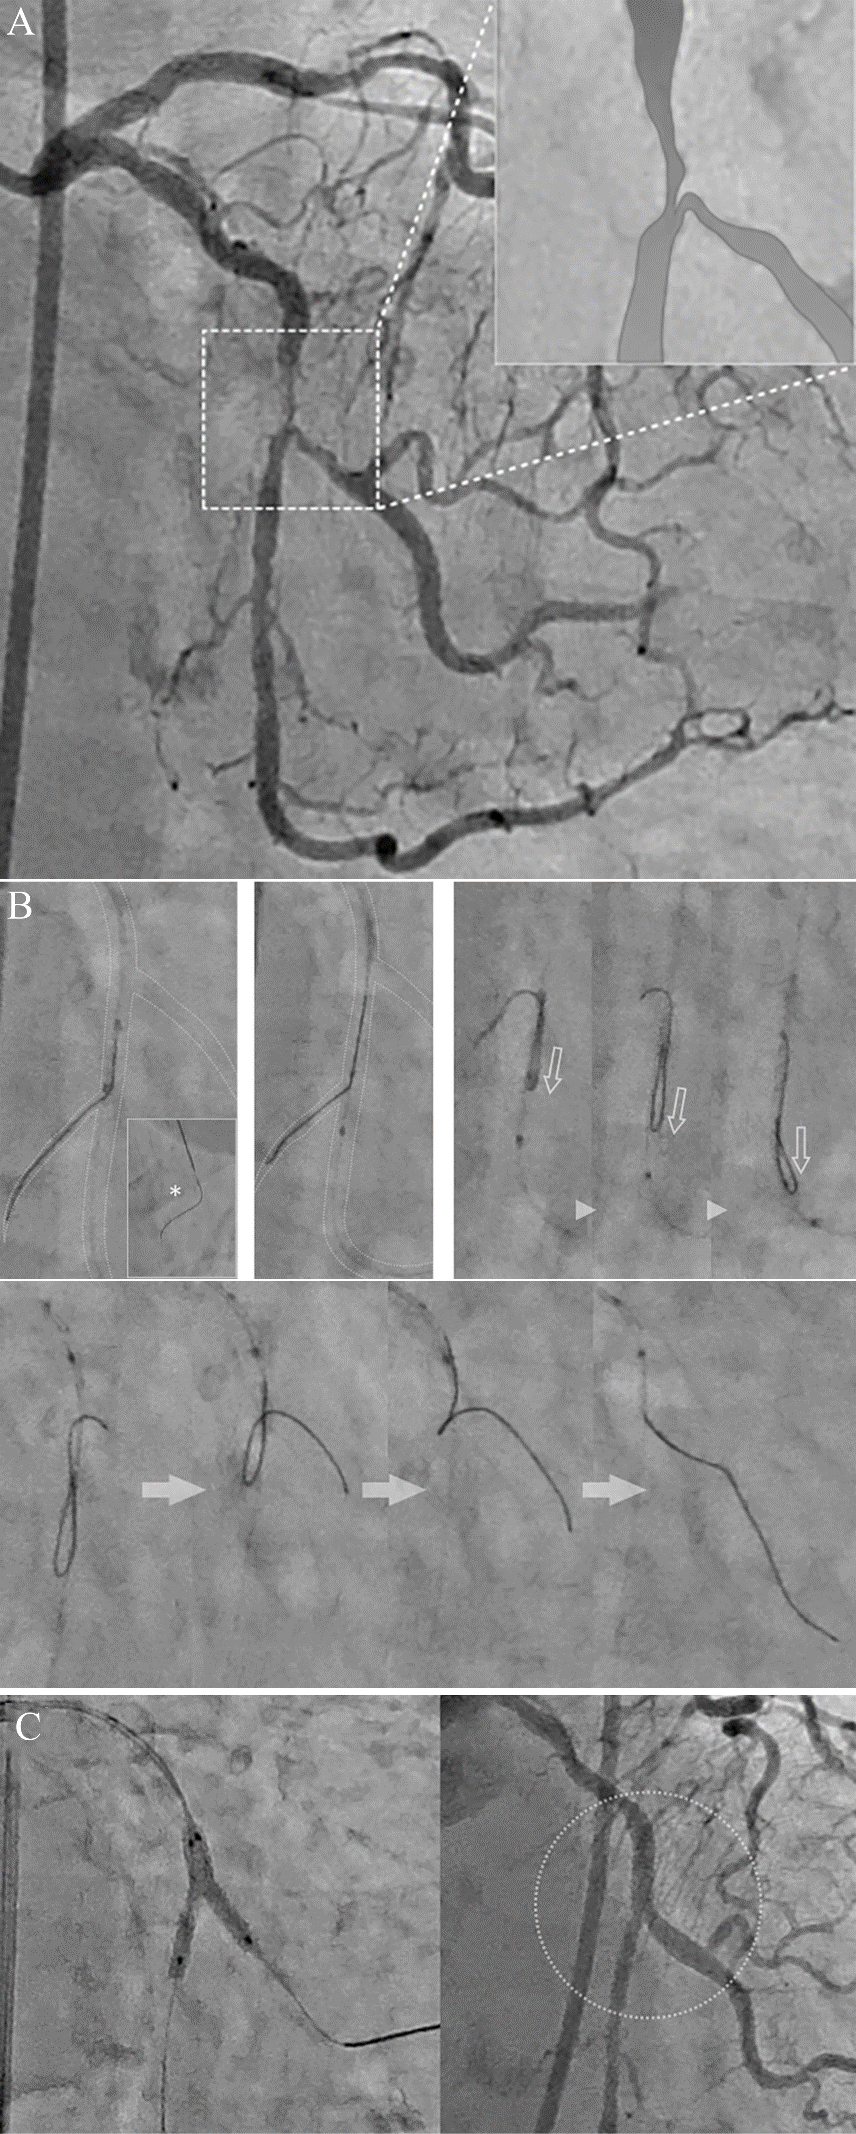

图1 体内反转导丝技术操作示意图[3]:A严重成角病变。B导丝通过分叉病变进入主支远端。C双腔微导管推送越过靶分叉;反转导丝体外预塑形,沿OTW腔送至靶分叉以远的某一分支(非靶分支)。D-F将双腔微导管的中心腔出口(侧孔)送至非靶分支的开口,同时将反转导丝的反折点也调整到非靶分支的开口处。E前送双腔微导管,反转导丝在前送力作用下逐渐反转,直至反转导丝脱离非靶分支。G-I其后操作同经典反转法。

图3 体内反转导丝技术辅助回旋支分叉病变PCI [3]。85岁女性,糖尿病和高脂血症,不稳定性心绞痛。造影示回旋支中段严重狭窄,累及极度成角的钝缘支(A)。右股动脉径路7 F AL1.5 指引导管到位,SION blue回旋支主支,钝缘支导丝难以进入。经典反转导丝技术难以施行,因为“反转导丝+双腔微导管”无法通过回旋支严重狭窄。 尝试进行体内反转导丝技术:双腔微导管(无反转导丝)推送越过靶分叉,沿OTW腔送入预塑形的反转导丝(距离前端25mm处90°反转弯,前端5mm正常塑形),送至靶钝缘支以远的心房支。将导丝的反折处和双腔微导管中心腔出口同时调整到心房支开口处,将“反转导丝+双腔微导管”作为一个整体同时前送,体内形成反转袢,直至反转导丝脱离心房支。其后操作同经典反转法:逐渐回撤“反转导丝+双腔微导管”,并微调反转导丝方向进入靶钝缘支。最终回旋支-钝缘支置入2.75×20mm支架并最终球囊对吻。